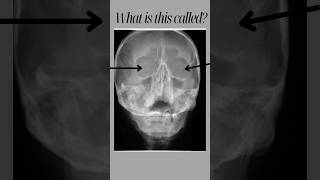

What is this called?#ytshorts #anatomy #medical #radiology #xray video

What is this called?#anatomy #ytshorts #xray #radiology What is this called?#anatomy #ytshorts #xray #sinus

What is this called?#anatomy #ytshorts #xray #sinus Reading a chest X-ray